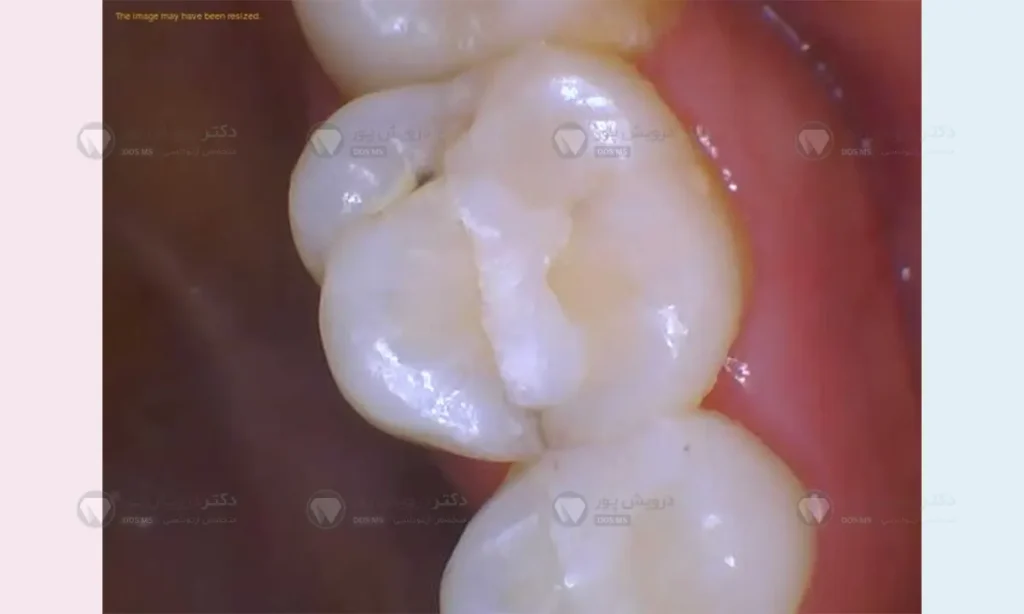

دسترسی به دندان

درمان ریشه از سطح جونده دندان های خلفی یا از سطح پشتی (زبانی) دندان های جلویی انجام می شود. خوشبختانه، براکت های ارتودنسی روی سطح بیرونی (گونه ای) دندان ها چسبانده می شوند. بنابراین، در بیشتر موارد، متخصص ریشه بدون اینکه سیم و براکت مزاحمتی ایجاد کند، می تواند به راحتی به دندان دسترسی پیدا کرده و کار خود را شروع کند.